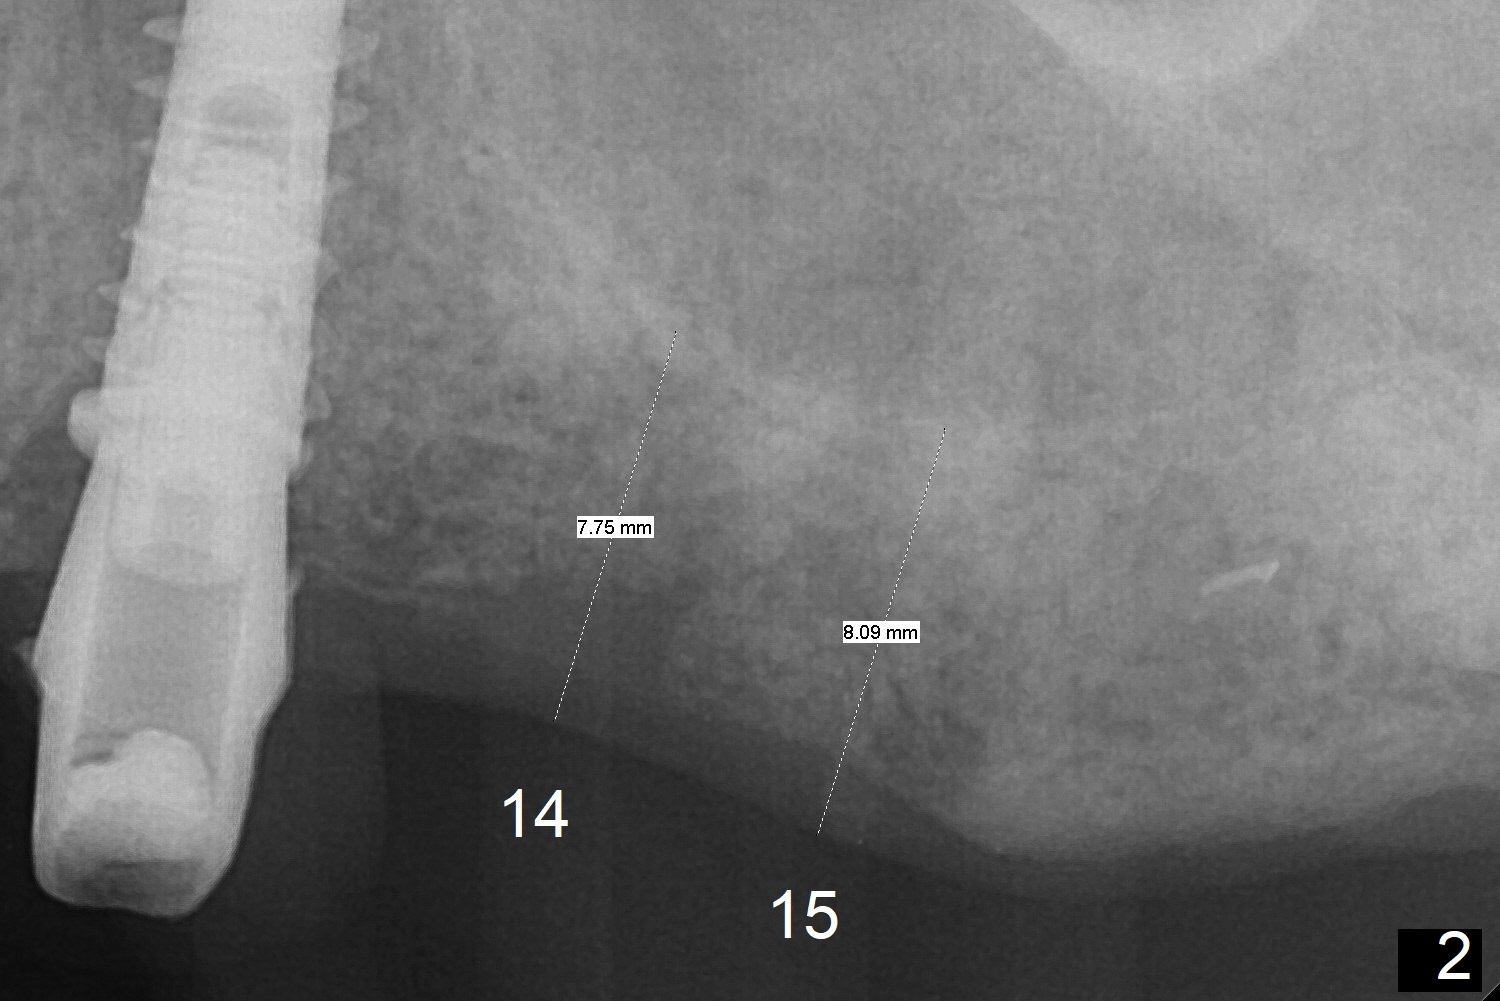

A 73-year-old man lost #15 implant 4 months ago with socket preservation (Fig.1 (taken 1 month post bone graft (^)). The tooth #14 was extracted with socket preservation ~ 9 months ago. The sites should be not so dense that Magic Split will be used to start osteotomy for 7 mm (Fig.2). Prior to this step, use 1.5 mm or starter drill and surgical stent to mark the initial osteotomy. BEB is followed by Magic Expanders (1 mm longer each). Implants are expected to be 9 or 11 mm long (Fig.3,4).